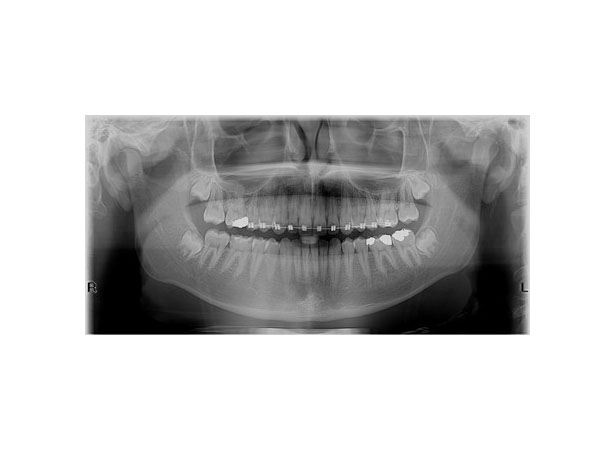

We perform all types of dental, jaw, sinus, and cervical vertebrae imaging, with the following three types being the most requested:

• Orthopantomogram (digital panoramic X-ray of the entire jaw)